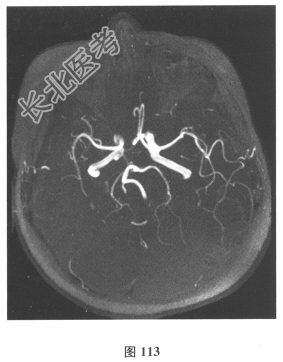

脑脊液检查:常规、生化均正常,CSF-病毒TORCH(-),抗Hu、Yo、Ri均阴性,OB、MBP正常。血清抗Hu、Yo、Ri均阴性。颅脑MRI显示左颞枕、右顶枕多发长T₁、长T₂信号,Flair高信号,病变累及皮质及皮质下白质,病灶无强化,见图108~图114。)根据颅脑MRI,需要鉴别的疾病应是